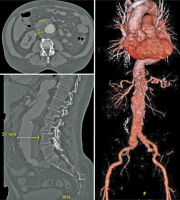

Aorta

Abbildung 2: Darstellung der thorakalen Aorta in axialer Schichtung mit Typ-B-Dissektion (nur deszendierende Aorta, oben links), mit Dissektion der aszendierenden und deszendierenden Aorta (Typ-A-Dissektion, unten links) sowie sagittale Darstellung des Verlaufs der Dissektionsmembran der Typ-A-Dissektion (rechts).

Keywords: AortaCT